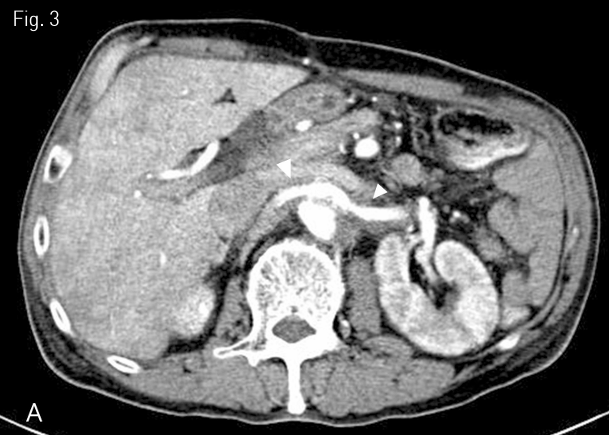

Fig 3A

Follow-up CT scan was undergone 1 week after the procedure (A) Improvement of the obstruction of both renal arteries with preserved lumen was noted (arrowheads).

Fig 3B

(B) The restoration of the right renal perfusion was observed (asterisk).